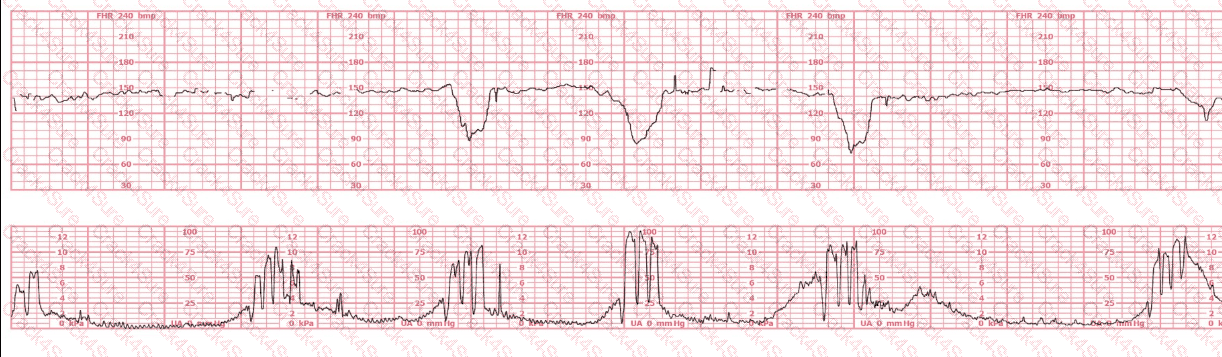

A 30-year-old woman (G2P0) is experiencing preterm labor at 26-weeks gestation. She is receiving magnesium sulfate for neuroprotection. Her external fetal monitoring tracing over the past 30 minutes is shown. The next step would be to:

A woman at 38-weeks gestation is admitted to labor and delivery following a fall down the stairs three hours ago. She started feeling contractions in the ambulance. The fetal heart rate tracing shown is on initial evaluation and represents 25 minutes. This tracing is most consistent with a

The decelerations seen in the fetal monitoring tracing shown are best described as:

A woman in labor has been pushing for 4 hours. For the last 2 hours, there have been recurrent variable decelerations. Variability has evolved from moderate to minimal. Cervical exam is 10/100%/+2, fetal head OP. There has been no fetal descent for the last 45 minutes. Based on the tracing shown, the most reasonable approach is